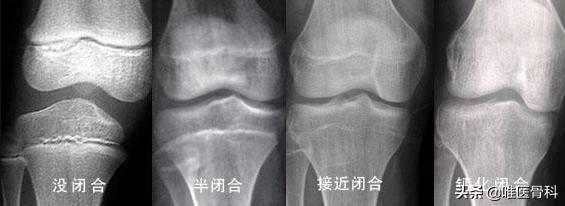

在一般情况下,女孩的骨骺闭合时间约16岁,男孩比女孩平均约晚2年也就是约18岁。

一旦骨骺闭合,无论任何方法,都不可能再长高。

新闻报道中这名25岁患者在医院就是通过检查发现其骨龄只有13岁且骨骺线还未闭合后发现其异常,最终才确诊的。

一般来说儿童骨龄龄=实际年龄±1年,骨骼的发育和人体内分泌及生殖系统的发育密切相关,通过测量儿童的骨龄,计算与实际年龄的差别,可以作为一些疾病的辅助诊断条件。

家长要随时关注孩子身高、骨龄,可以及时掌握孩子的发育情况,一般建议在青春期结束之前每隔3个月为孩子测量并记录身高,可以每年或每两年为孩子检查一次骨龄。